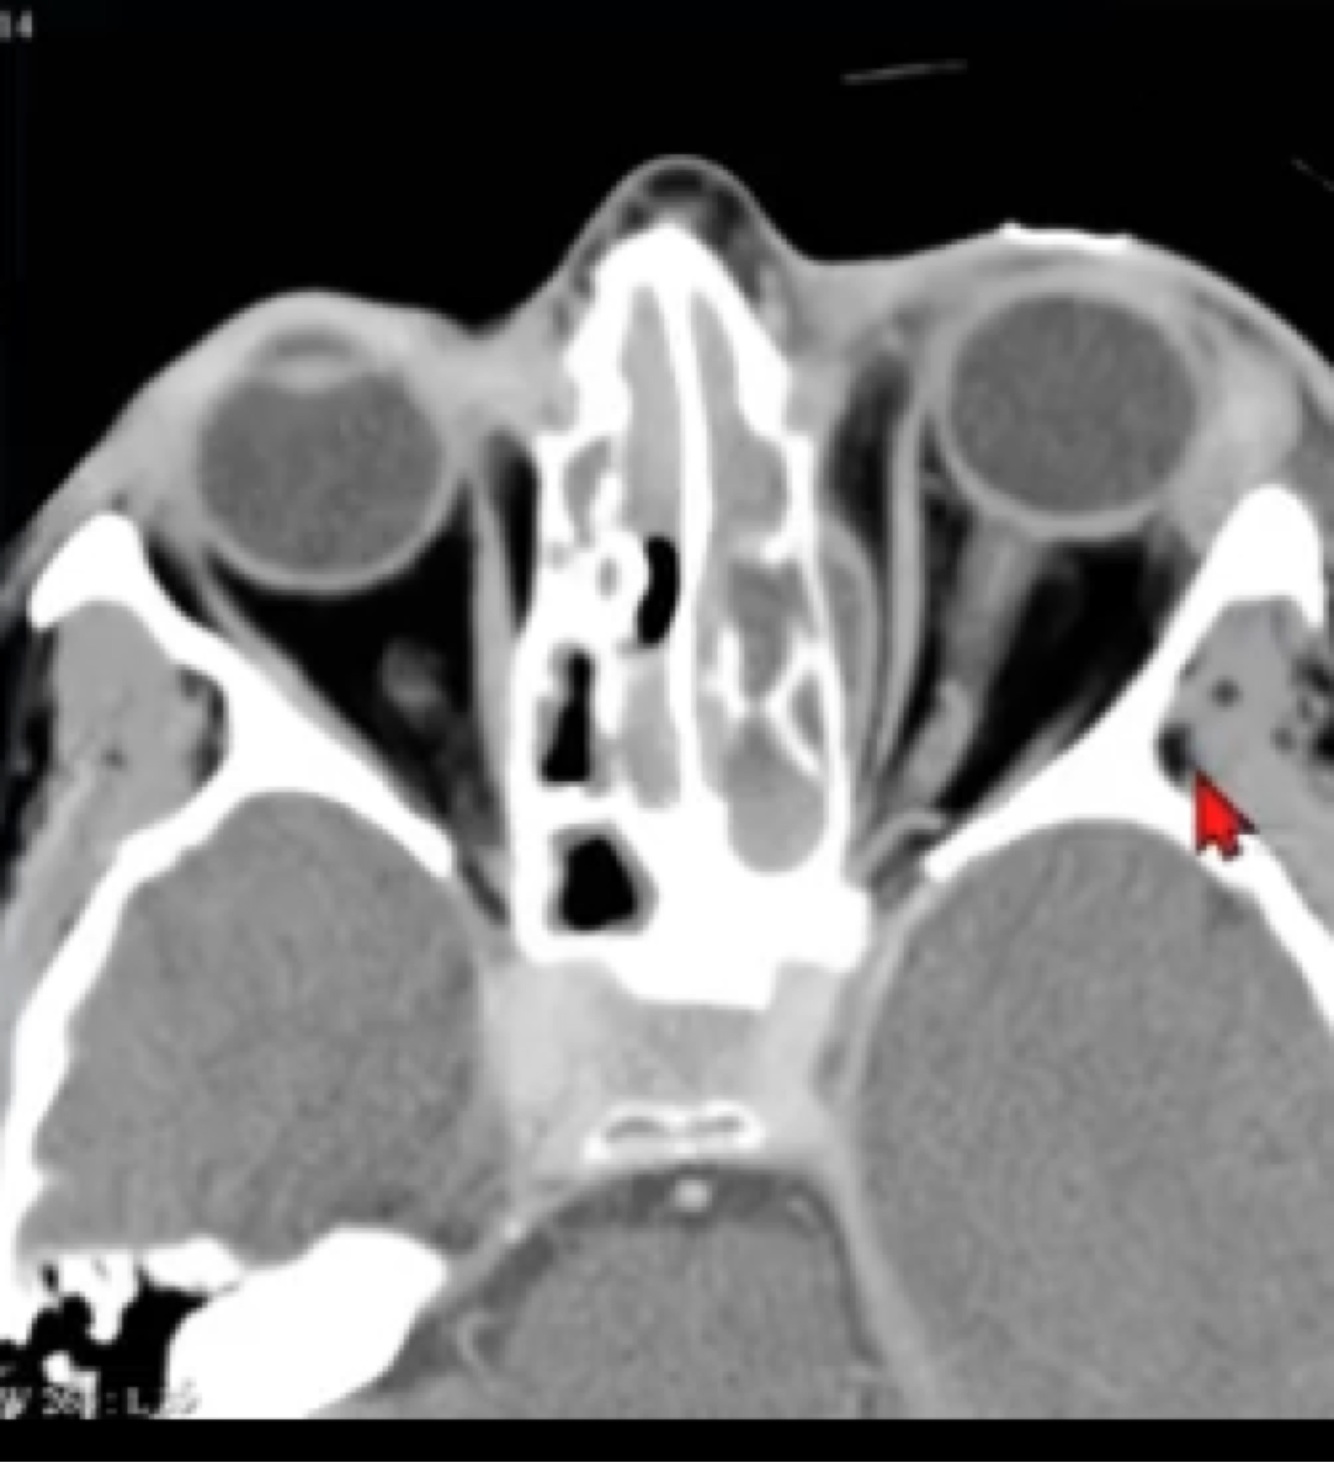

Achado a seguir:

A

Sinusite e abscesso orbitário esquerdo.